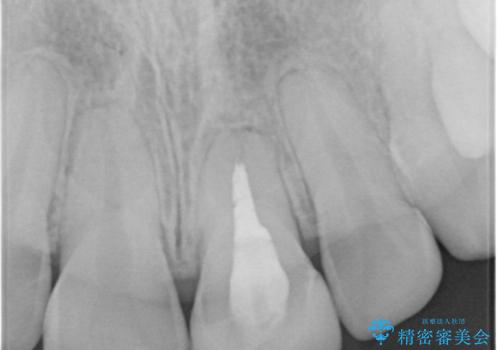

- 「左上の前歯の色が変色し、セラミッククラウンで治したい」とのことで、来院された患者様です。過去に神経の治療(根管治療)をされており、それにより歯の色が変色していました。

左上の前歯(左上1)は、歯の形を整えてオールセラミッククラウンという被せ物で、変色の改善を行いました。

変色していた左上の前歯は、過去に神経の治療(根管治療)をされており、それにより歯の色が変色していました。

根管治療を行った歯は、破折するリスクがあるため、被せ物をすることで、破折リスクの軽減にもなるため、被せ物で歯の色の改善を行いました。